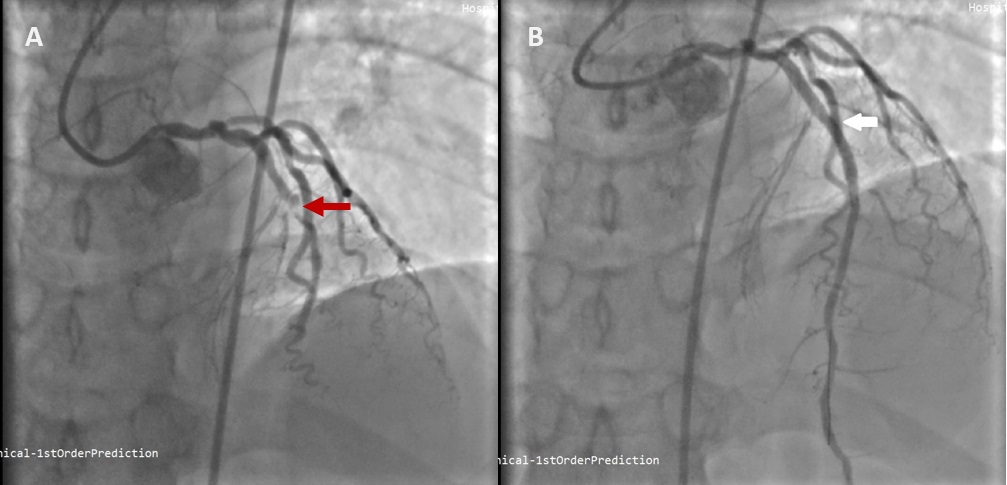

De Winter syndrome is a rare but important ST-elevation myocardial infarction (STEMI) equivalent, that is characterised by severe stenosis of the left anterior descending artery (LAD). It can be easily misdiagnosed due to its atypical electrocardiogram (ECG) pattern which causing a delay in reperfusion, hence increases risk of mortality. Herein, we reported a 38-year-old man presented to the emergency department (ED) with initial ECG showed hyperacute T wave, which later evolved to de Winter syndrome ECG pattern after serial ECG were done. He was immediately referred to the cardiology team and underwent immediate percutaneous coronary intervention (PCI) to revascularise the stenosis found at the left anterior descending artery (LAD). He showed good outcomes and no complication after the procedure. This paper aimed to shed light on the importance of early identification, right diagnosis and treatment in De Winter syndrome case to avoid complications.